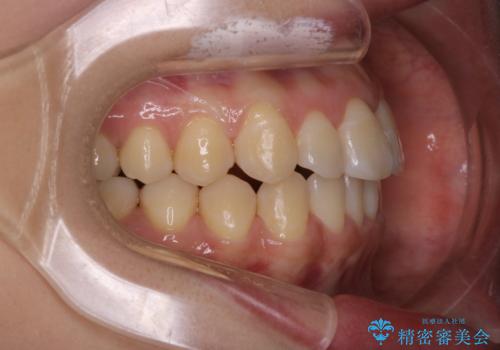

- メタル装置

- 前歯のがたつきを治したいという主訴で来院されました。1年後に転勤の可能性があり短期間での治療を希望されました。今回は非抜歯の治療を計画し、IPRと拡大をし、前歯の叢生を改善しました。

前歯のがたつきを治しながら2番の反対咬合も改善させました。短期間で終了し満足していただけました。